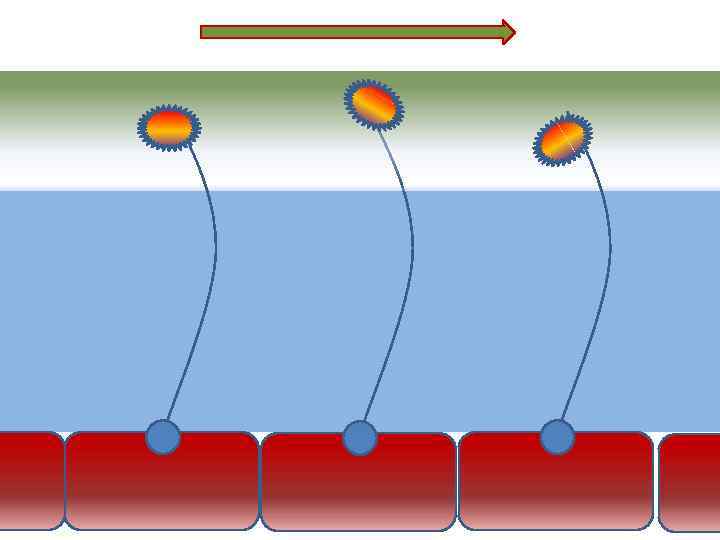

Механизм защиты легкого Слизь (зеленый цвет) нейтрализует и связывает патогенную флору(синий цвет) Слизь – это барьер между клетками и патогенной флорой Слизь – это транспортное средство

Механизм защиты легкого Слизь (зеленый цвет) нейтрализует и связывает патогенную флору(синий цвет) Слизь – это барьер между клетками и патогенной флорой Слизь – это транспортное средство